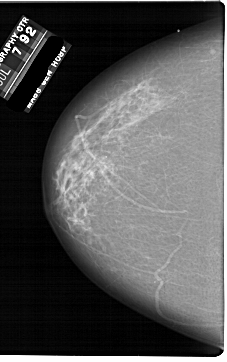

A_1861_1.LEFT_MLO

LEFT_MLO LINES 6136 PIXELS_PER_LINE 4726 BITS_PER_PIXEL 12 RESOLUTION 43.5 NON_OVERLAY